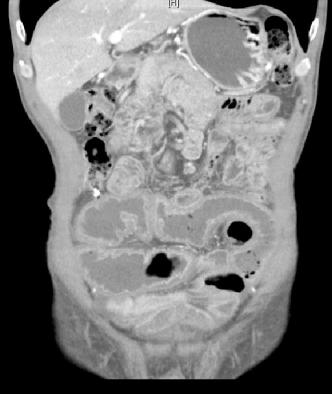

术前腹部CT可见盆腔部位肠管肠壁水肿、纤维化,近端肠管扩张。